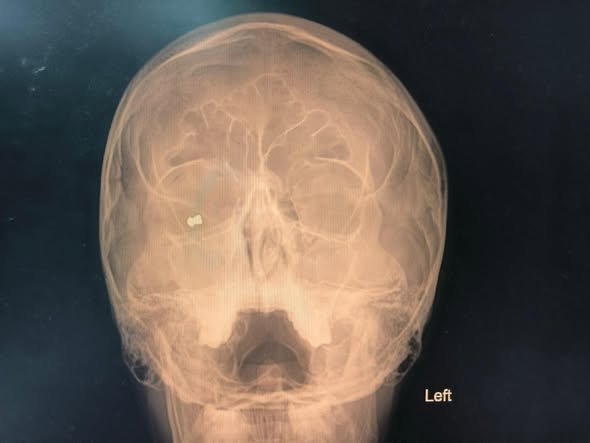

При осъществения незабавен офталмологичен обзор е открито железно непознато тяло в орбитата на дясното око, както и разкъсна рана на клепача, съответстваща на входно отвърстие от прострелване. Зрението на пациента все още на приемане е било мощно понижено – до преброяване на пръсти пред окото.

След цялостни проучвания и подготовка, екипът на доцент Яни Здравков прави незабавна интервенция, при която сполучливо е отстранено железно непознато тяло – съчма от въздушна (газова) пушка.